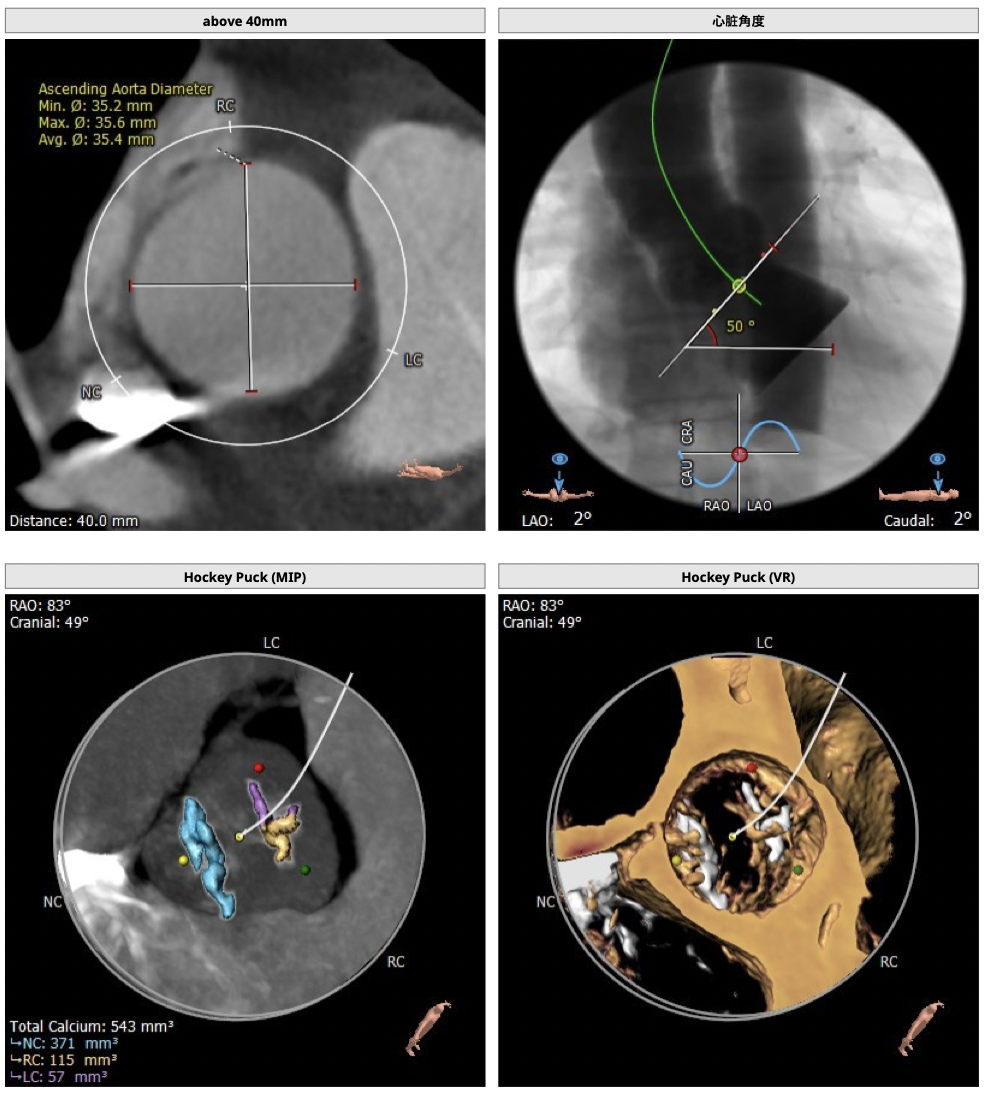

图片

术中影像

根部造影

球囊预扩

释放瓣膜

瓣膜释放至2/3造影观察

瓣膜释放完毕

手术结果

术后造影及超声探查未见瓣周漏,跨瓣压差术前108mmHg,术后几乎无压差,术中及术后未出现相关并发症,手术圆满完成。